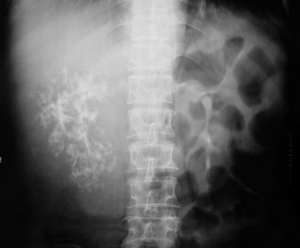

(1)X線檢查:本病的X線改變很不一致,各種各樣的局灶或瀰漫性損傷均可見,且取決於有無梗阻結石和其他異常的存在。80%的患者IVP可發現帶有結石的病腎不顯影,腎盞變形也常見尤其病腎為瀰漫性者。局灶性損傷者表現為囊性或腫塊內空洞其中充盈缺損。